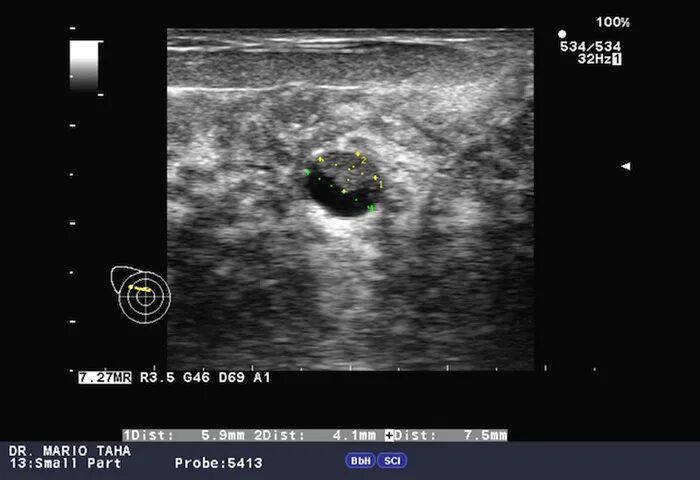

Как выглядит киста молочных желез